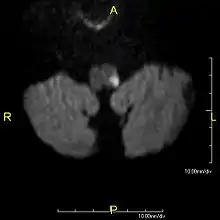

Since lateral medullary syndrome is often caused by a stroke, diagnosis is time dependent. Diagnosis is usually done by assessing vestibular-related symptoms in order to determine where in the medulla that the infarction has occurred. Head Impulsive Nystagmus Test of Skew (HINTS) examination of oculomotor function is often performed, along with computed tomography (CT) or magnetic resonance imaging (MRI) to assist in stroke detection. Standard stroke assessment must be done to rule out a concussion or other head trauma.[2]

- MRI of Lateral Medullary Infarction (Wallenberg) MedPix Images